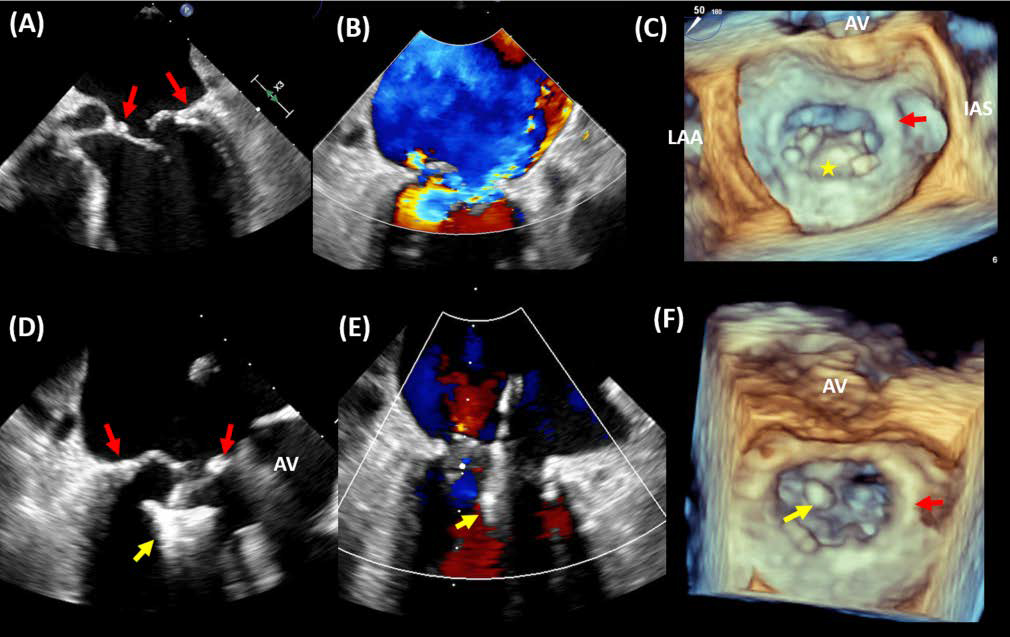

Single leaflet device attachment (SLDA) describes and entity in which there is disengagement of insertion of one of the leaflets from the MitraClip device and can occur in 2–5% of cases. This entity can occur during the procedure or follow-up [17, 18, 42, 45]. One of the most important tasks of the structural heart imager entails the acquisition of high-resolution grasping views that display leaflet insertion into clip arms ensuring a good grasp with both leaflets tucked in the closed device. Some strategies to stabilize SLDA include the deployment of additional clips if feasible [40, 47, 48]. Fig. 5 shows TEE imaging demonstrating the attachment of the clip to a single leaflet.

Fig. 5.Single leaflet detachment. A case of single leaflet device attachment (SLDA). A patient with previous transcatheter edge-to-edge repair of the mitral valve presents with heart failure symptoms and TEE imaging showing SLDA of the MitraClip device (yellow arrow). The device was attached to the anterior leaflet (A&B) with severe mitral regurgitation (C). A second MitraClip device (red arrow) was deployed medial to the first device, resulting in mild residual MR (D). 3 TEE imaging shows the newly implanted device at A3-P3 in relation to the first device that has detached from the posterior leaflet (E). AV, aortic valve; LAA, left atrial appendage; IAS, interatrial septum.